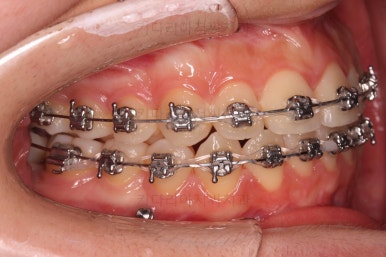

부산교정 키다리아저씨치과에 처음 내원하셨을 당시의 입안 모습과 X-ray 사진입니다.

초진 시 다른 부위들 사진입니다.

약간의 주걱턱 느낌에 약간의 돌출감, 전반적인 치열의 가지런한 느낌은 나쁘지 않았지만 약간의 불량한 교합상태였어요.

다른 부분은 크게 바꾸지 말고 약간의 교합조절과 어금니 치료에 초점을 맞춰서 교정치료 계획을 잡았습니다.

이번에 사용한 장치는 엠파워메탈이라고 하는 자가결찰(철사를 잡아주는 뚜껑이 달려있는) 메탈(금속 성분) 장치였어요.

매우 장점이 많으나 심미성과 재료제작 비용 때문에 상대적으로 저렴한(이것도 장점일 수 있죠.) 장치입니다.

장치를 부착했을 때 입이 나오는 느낌, 웃을 때 느낌은 참고해 주세요.